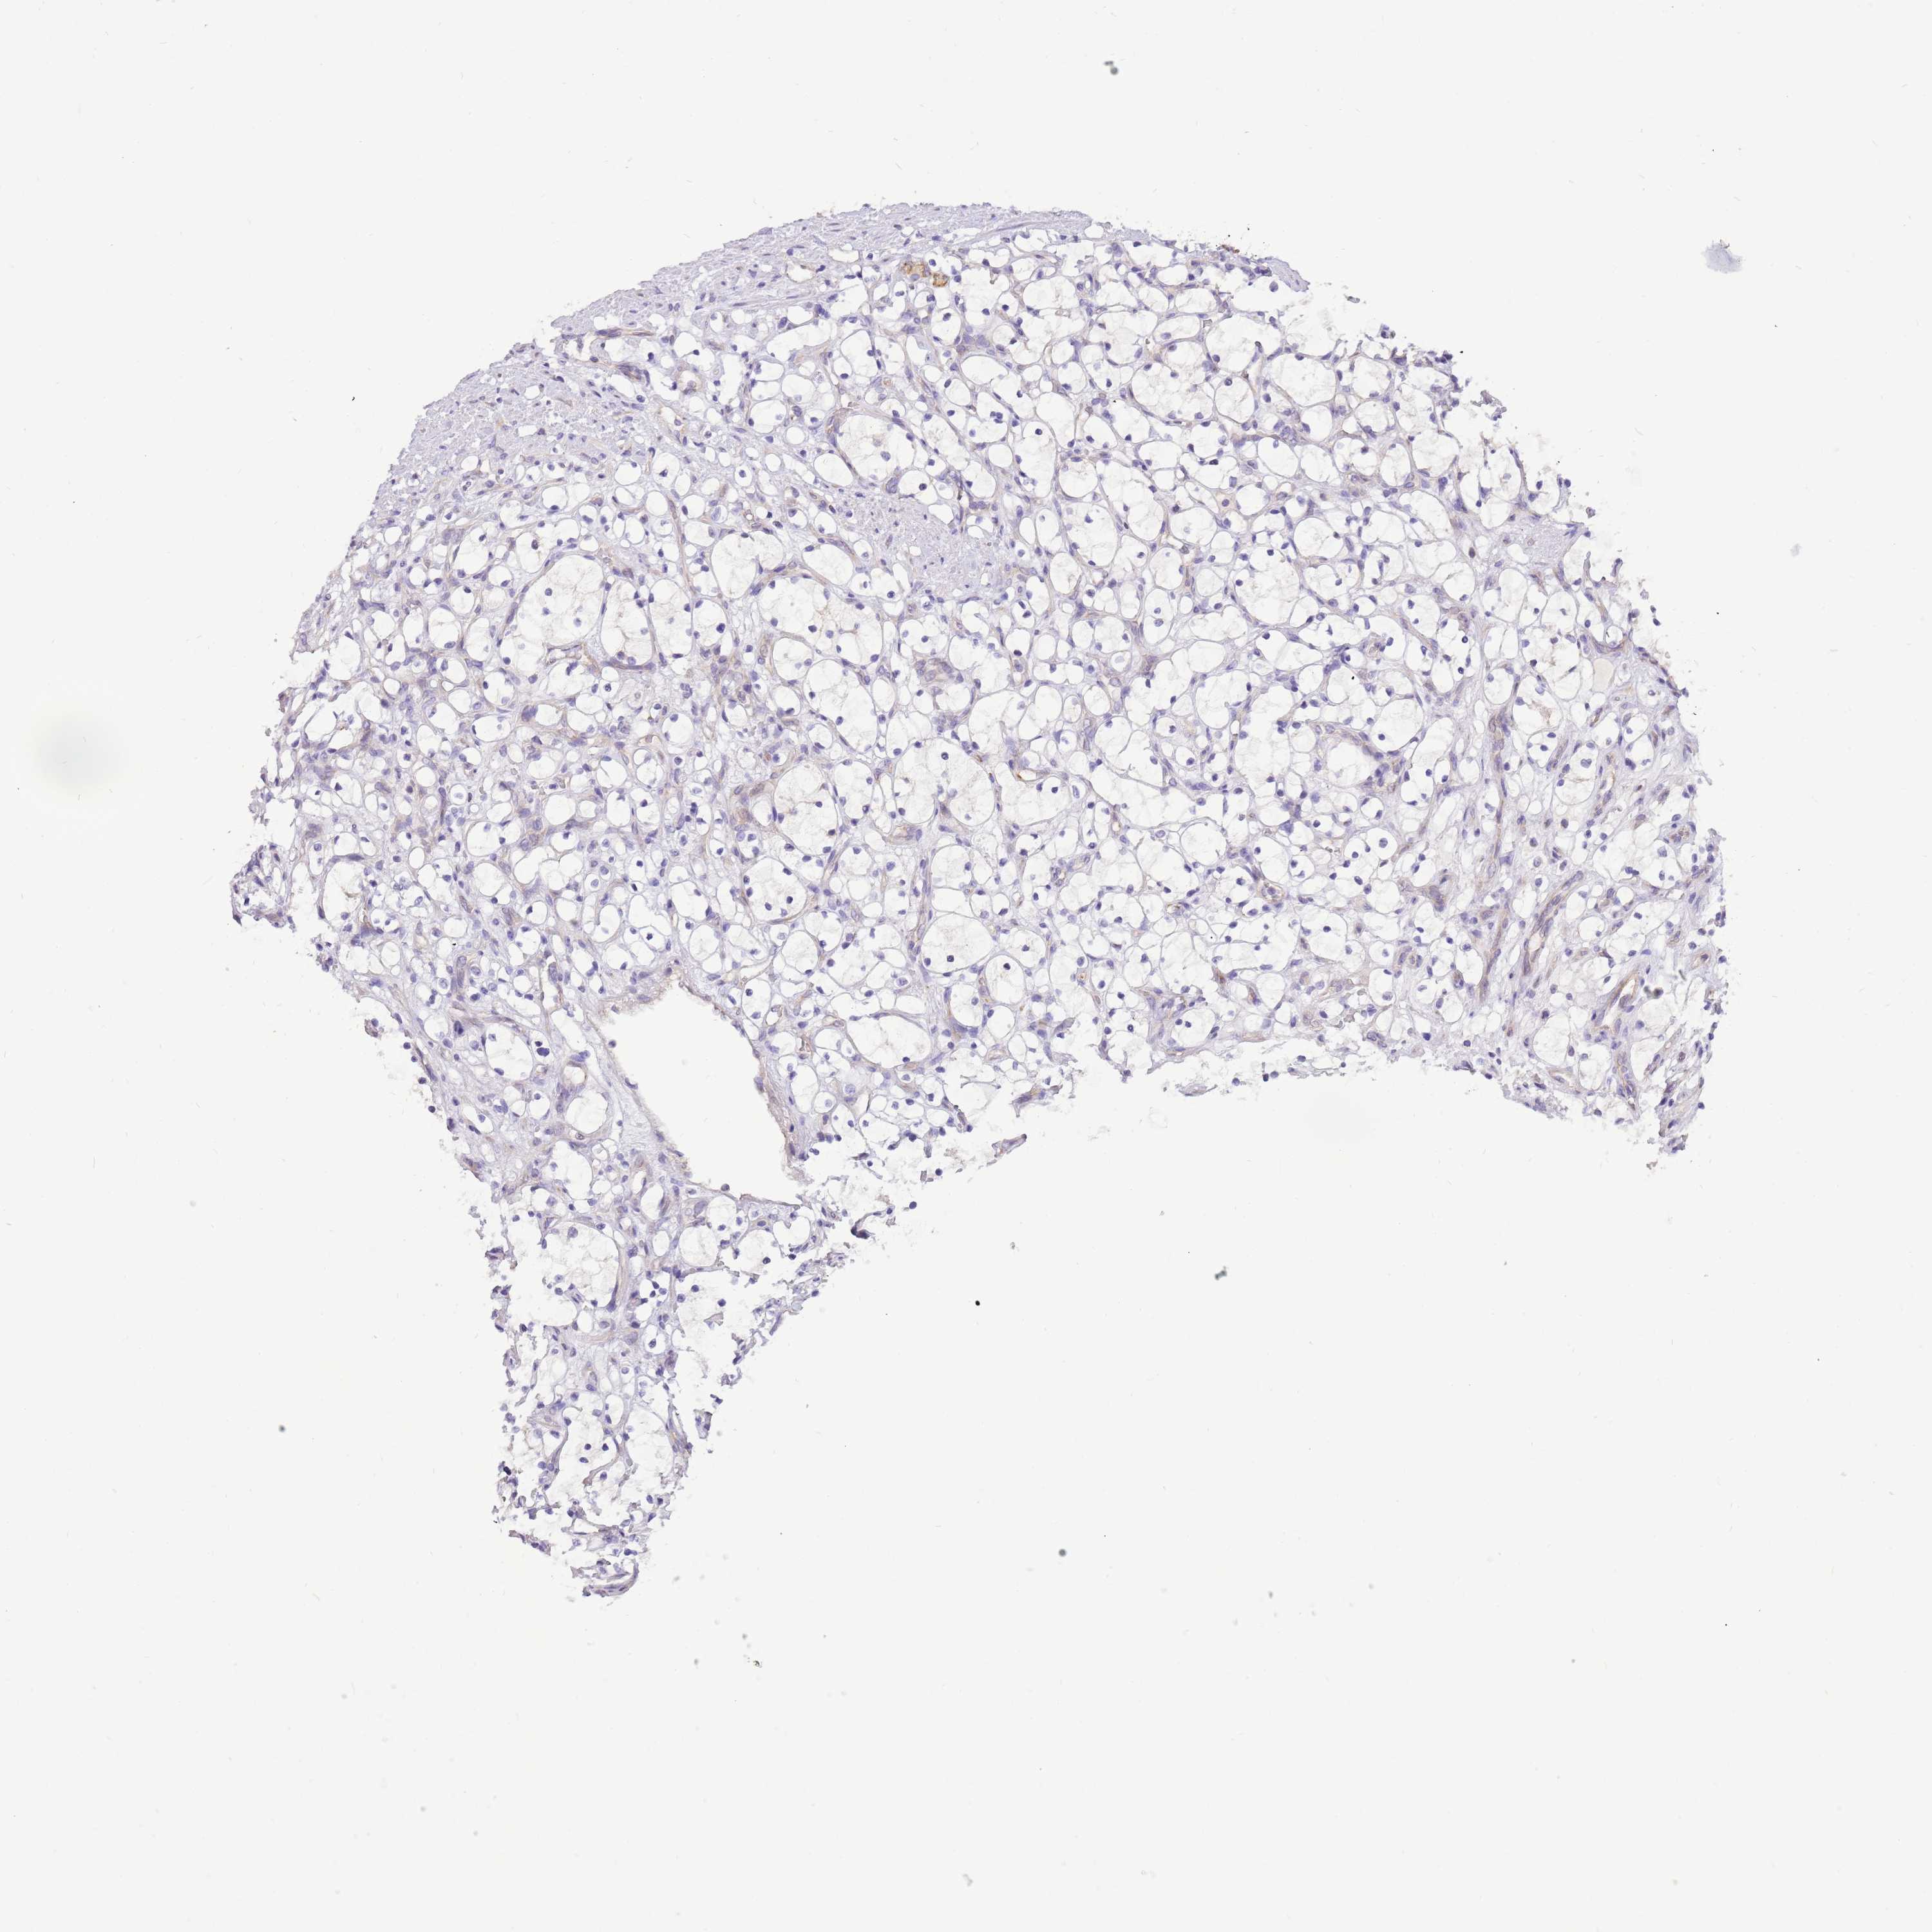

KIDNEY RENAL CLEAR CELL CARCINOMA (VALIDATION) - Interactive survival scatter ploti

The Survival Scatter plot shows the clinical status (i.e. dead or alive) for all individuals in the patient cohort, based on the same data that underlies the corresponding Kaplan-Meier plots. Patients that are alive at last time for follow-up are shown in blue and patients who have died during the study are shown in red.

The x-axis shows the expression levels (FPKM) of the investigated gene in the tumor tissue at the time of diagnosis. The y-axis shows the follow-up time after diagnosis (years). Both axes are complimented with kernel density curves demonstrating the data density over the axes. The top density plot shows the expression levels (FPKM) distribution among dead (red) and alive patients (blue). The right density plot shows the data density of the survived years of dead patients with high and low expression levels respectively, stratified using the cutoff indicated by the vertical dashed line through the Survival Scatter plot. This cutoff is automatically defined based on the FPKM cutoff that minimizes the p-score. The cutoff can be changed by dragging the vertical line or by entering a cutoff value in the square labeled "Current cut-off".

Under the Survival Scatter plot the p-score landscape (black curve; left axis) is shown together with dead median separation (red curve; right axis). Dead median separation is the difference in median mRNA expression between patients who have died with high and low expression, respectively. It is calculated as follows: median FPKM expression of dead patients with high expression - median FPKM expression of dead patients with low expression. This is intended to aid the user in visually exploring custom cutoffs and the associated p-scores and dead median separation.

Individual patient data is displayed and can be filtered by clicking on one or more of the category buttons on the top of the page. Categories describing expression level and patient information include: high, low, alive, dead, female, male and tumor stages. The scale of the x-axis can be toggled between linear and log-scale by clicking on the "x log" button. Mouse-over function shows TCGA ID, patient information and mRNA expression (FPKM) for each patient.

& Survival analysisi

Kaplan-Meier plots summarize results from analysis of correlation between mRNA expression level and patient survival. Patients were divided based on level of expression into one of the two groups "low" (under cut off) or "high" (over cut off). X-axis shows time for survival (years) and y-axis shows the probability of survival, where 1.0 corresponds to 100 percent.

COX17 is not prognostic in Kidney Renal Clear Cell Carcinoma (validation)

Best expression cut offi

Based on the FPKM value of each gene, patients were classified into two groups and association between prognosis (survival) and gene expression (FPKM) was examined. The best expression cut-off refers the FPKM value that yields maximal difference with regard to survival between the two groups at the lowest log-rank P-value. Best expression cut-off was selected based on survival analysis .

When clicking on this number, the vertical dashed line indicating cut-off, the interactive survival plot, and the Kaplan-Meier curve will be adjusted to show results based on the best expression cut-off.

: 149.67

Median expressioni

Median expression refers to the median FPKM value calculated based on the gene expression (FPKM) data from all patients in this dataset. When clicking on this number, the vertical dashed line indicating cut-off, the interactive survival plot, and the Kaplan-Meier curve will be adjusted to show results based on the median expression.

: N/A

Median follow up timei

Median follow up time refers to the median time (years) after diagnosis with this type of cancer, based on clinical data from all patients in this dataset.

P scorei

Log-rank P value for Kaplan-Meier plot showing results from analysis of correlation between mRNA expression level and patient survival.

N/A

5-year survival highi

5-year survival for patients with higher expression than the expression cutoff.

For melanoma and glioma, 3-year survival is shown.

5-year survival lowi

5-year survival for patients with lower expression than the expression cutoff.

TCGA RNA samplesi

RNA-seq data is reported as average FPKM (number Fragments Per Kilobase of exon per Million reads), generated by the The Cancer Genome Atlas (TCGA) .

Normal distribution across the dataset is visualized with box plots, shown as median and 25th and 75th percentiles. Points are displayed as outliers if they are above or below 1.5 times the interquartile range. FPKM values of the individual samples are presented next to the box plot.

Average pTPM 136.1

Number of samples 100